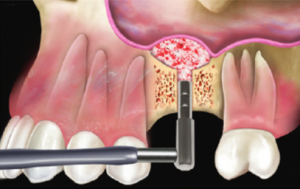

4. Quindi viene sollevata delicatamente la membrana, che ricopre internamente tutto il seno mascellare. |

5. Successivamente viene introdotto dell’osso artificiale all’interno del seno mascellare. |

6. A questo punto viene inserito l’impianto, che viene stabilizzato grazie all’osso pre-esistente, ma che, nei mesi successivi, formerà un tutt’uno con l’innesto di osso. |